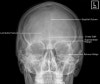

1. Adult Skull - PA 0 Degree Angulation

- Adult Skull - PA 15 Degree Angulation (Caldwell)